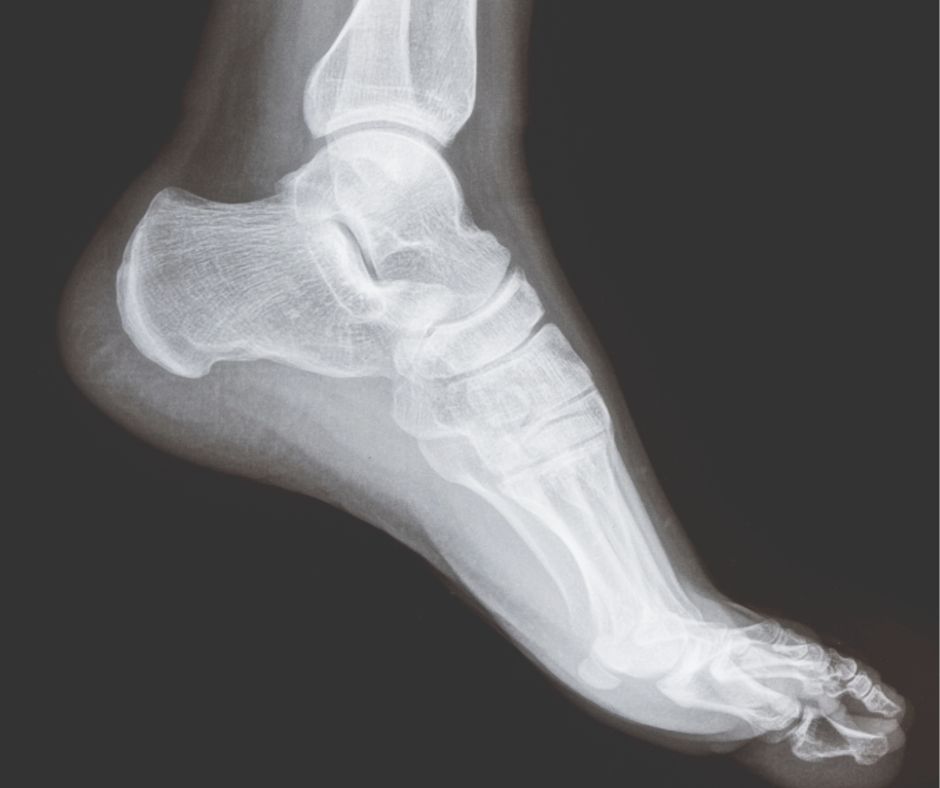

When to Refer for Imaging: X-ray in Foot and Ankle Pain

X-ray imaging remains a fundamental first-line investigation in the assessment of foot and ankle pain. While not all patients require imaging, understanding when to refer for radiographs is essential in identifying structural pathology, guiding management, and avoiding missed diagnoses. X-rays are particularly useful in evaluating bony structures, joint alignment, and degenerative change. Common indications include…